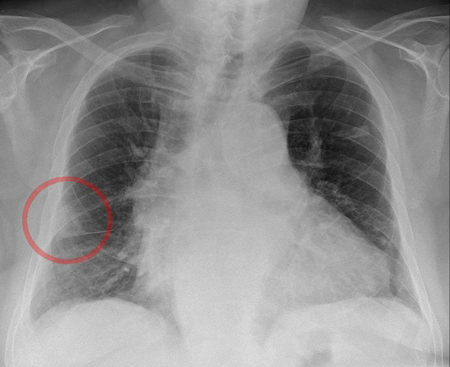

A 60-year-old female presents with shortness of breath, fevers, and severe pleuritic pain for the past 3 days. She has been mostly in bed due to a hip fracture. Her past history includes depression and anxiety.

- Hampton’s Hump Sign

- Pulmonary embolism cuts off blood supply to the lungs. The hump is a wedge-shaped area of lung tissue infarct and hemorrhage from bronchial arteries.

- This sign is characteristic of pulmonary embolism. However, absence of this sign does NOT rule out pulmonary embolism.